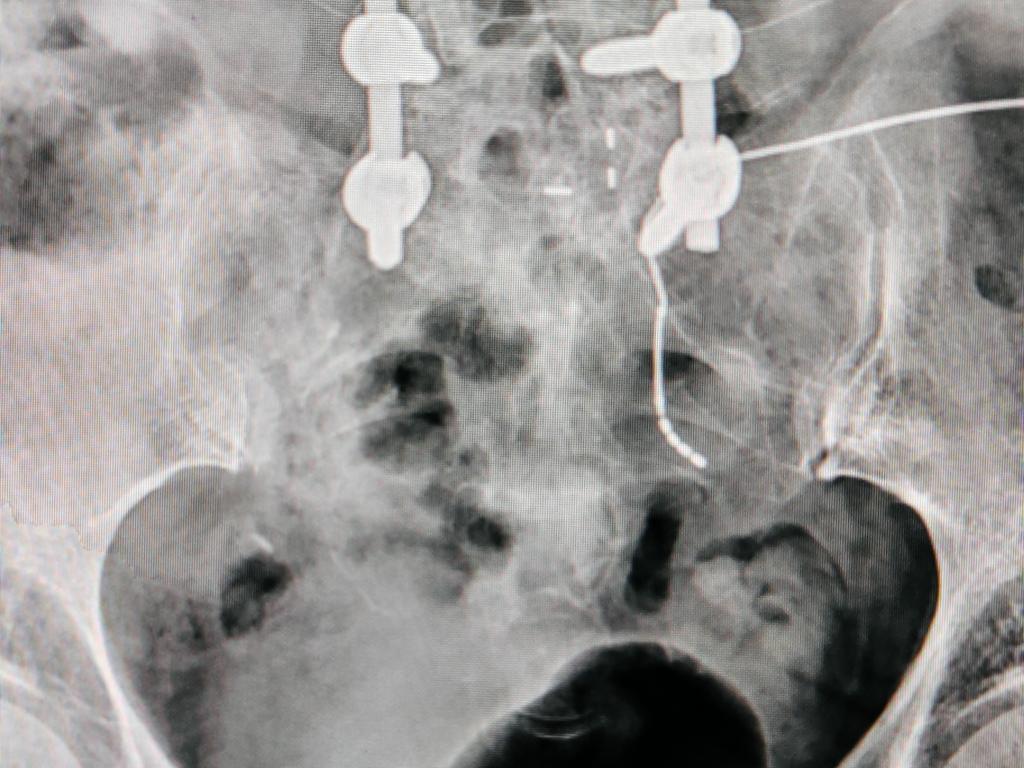

骶骨三维重建 超声引导下定位

完全脱离X线穿刺、术中测试与磁共振兼容电极置入

经术中超声辅助定位、术中测试,确认患者双侧S3神经感觉与运动应答均较差,左侧S2测试患者获得了“左侧臀部、大腿根部及肛门周边感觉良好应答、左侧足底跖屈反射刺激应答明确且无腓肠肌震颤、在增加脉宽后会阴部左侧区域感觉应答明确”,依据西安交大二附院“尿控与盆底修复”诊疗团队在完全脱离X线-B超辅助定位骶神经调控疗法个体化手术经验,术中确定选择患者左侧S2神经孔置入电极并确认深度并精准释放,术中最低测试电压0.5V,等待患者术后体验治疗24小时、完成X线电极定位复查,开始骶神经调控Stage1体验治疗。

临时刺激器连接并开机 SNM Stage1术中24小时X线复查